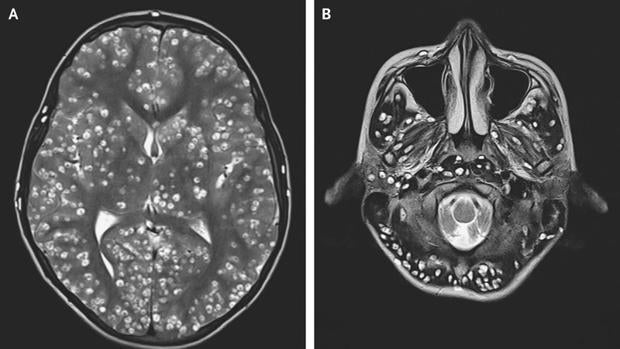

29/03/2019 17:39h. Muere por una infestación de larvas de tenia en el cerebro tras comer carne cruda ABC

29/03/2019 17:38h. Muere a causa de una infestación de larvas en el cerebro que contrajo al comer carne cruda